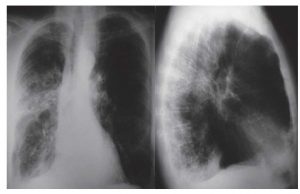

Se ha realizado en ocho Unidades de Cuidados Intensivos (UCI) de seis hospitales de Canarias determinándose los niveles sanguíneos de guanina oxidada de pacientes covid al ingreso en UCI.

Los pacientes que fallecieron en los primeros 30 días de estudio presentaron al ingreso en UCI mayores niveles de guanina oxidada. La mortalidad era mayor también en los pacientes con niveles séricos más altos.

En esta última publicación se concluye que existe una asociación entre el daño oxidativo del ADN y el ARN (evaluado por la concentración sanguínea de guanina oxidada) y la mortalidad.